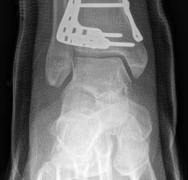

When a diaphyseal fracture propagates into the distal articular block, the injury transcends the typical treatment algorithms reserved for isolated tibial shaft fractures. Intramedullary nailing, the gold standard for diaphyseal fractures, becomes fraught with complications such as articular malreduction, propagation of intra-articular fracture lines, and inadequate distal fixation. Therefore, plate fixation—often utilizing minimally invasive percutaneous plate osteosynthesis (MIPPO) techniques—emerges as the primary definitive treatment modality. In the setting of an AO/OTA 43C3.3 fracture, where the articular surface is multifragmentary and completely dissociated from the diaphysis, the surgeon must meticulously reconstruct the joint surface before bridging the diaphyseal segment.

The CT scan allows the surgeon to map the fracture lines, identify the primary articular fragments (Chaput, Volkmann, medial malleolus), and quantify the degree of central die-punch impaction. In an AO/OTA 43C3.3 fracture, where no articular fragment is in continuity with the diaphysis, the surgeon must plan the sequence of reduction. Typically, the fibula is addressed first to restore lateral column length and rotation, provided the fibular fracture is not located at the level of the syndesmosis where fixation might interfere with the lateral surgical approach to the tibia.

Digital templating is utilized to select the appropriate implant. For a fracture extending into the diaphysis, an extra-long anatomical distal tibia locking plate is required. The surgeon must determine whether an anterolateral or medial plate (or dual plating) will provide the optimal biomechanical construct based on the fracture morphology. The trajectory of the distal locking screws must be planned to provide a subchondral raft supporting the articular surface without penetrating the joint space. Furthermore, the availability of bone graft or orthobiologics must be confirmed, as elevating impacted articular segments will leave a metaphyseal void requiring structural support.

Once the articular surface is visually and fluoroscopically reduced, the resultant metaphyseal void is densely packed with cancellous allograft, autograft, or synthetic bone substitute to prevent late subsidence. The major articular fragments (Chaput, Volkmann, and medial malleolus) are then reduced around the central reconstructed block using pointed reduction forceps. Provisional fixation is achieved with multiple 1.6mm or 2.0mm Kirschner wires. Independent 3.5mm or 4.0mm lag screws can be placed outside the planned footprint of the definitive plate to secure the articular block.

The distal portion of the plate is secured to the reconstructed articular block. It is imperative that the distal locking screws are placed parallel to the joint space, forming a rigid subchondral raft that supports the articular cartilage. Fluoroscopy is utilized extensively to ensure no screws have penetrated the joint. Once the distal block is secured to the plate, the diaphyseal segment is aligned. Length, alignment, and rotation are restored using manual traction or the femoral distractor. The proximal portion of the plate is then secured to the diaphysis using a combination of non-locking screws (to pull the bone to the plate) and locking screws (to create a fixed-angle construct). The working length of the plate is maximized by leaving several screw holes empty over the zone of comminution, promoting secondary bone healing.